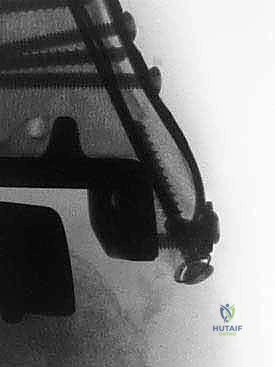

علاج هذه الكسور يتطلب مهارة فائقة من الدكتور محمد هطيف، حيث يتم استخدام تقنيات الجراحة الميكروسكوبية وتثبيت الكسور باستخدام صفائح معدنية دقيقة ومسامير (Locking Plates) دون المساس بثبات المفصل الصناعي، أو يتم دمج علاج الكسر ضمن عملية مراجعة المفصل الكلية إذا كان المفصل نفسه تالفاً.

يتم إدخال المفصل الجديد المخصص للمراجعة، والذي يحتوي غالباً على سيقان (Stems) تدخل عميقاً في عظمة الساق وعظمة الكاحل لضمان الثبات الميكانيكي. في حال وجود كسور في الكعب، يتم تثبيتها في هذه المرحلة.